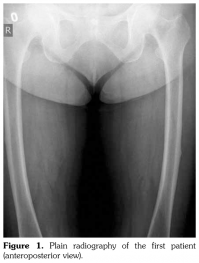

Case 1– A 73-year-old female patient presented with low back, knee, and anterior thigh pain. Pain severity was 8 over 10 point according to visual analog scale. She had difficulty in walking because of pain. She had a history of arthroscopic knee surgery for meniscal pathology in her left knee five years ago. She had chronic low back pain due to L4-5 disc herniation and lumbar spinal stenosis. She had been treated for osteoporosis with alendronate for two years, then with salmon calcitonin for two years and ibandronic acid for a year. Neurological examination was normal. Plain radiographs revealed bilateral lateral cortical thickening in the femur (Figure 1). Magnetic resonance imaging was done to rule out fracture. Bone scintigraphy showed increased uptake in bilateral femoral diaphysis. Routine biochemical tests were normal except increased urinary deoxypyridinoline. Urinary deoxypyridinoline level was 63 nM/mMCre (normal range: 3-7.4 nM/mMCre).